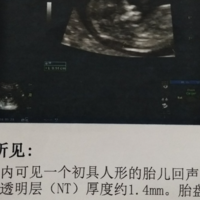

在孕期产前检查中,胎儿颈项透明层(Nuchal translucency,NT)是一项非常重要的指标。NT是通过B超技术在10-14周孕周内测量的,它是指位于胎儿颈部皮下的液体层的厚度。NT值的大小与胎儿染色体异常的风险密切相关,此外,也有人认为NT值的大小可以预测胎儿男女。那么,NT1.1mm是男孩还是女孩?接下来,我们一起来探讨一下。NT值与胎儿染色体异常风险正常情况下,NT值应该在2.5mm

怀孕11周的nt值1.1mm在正常范围内。正常女性怀孕11周-12周的NT正常值为小于3mm,1.1mm属于正常值,不必过于担心。NT值是指由胎儿颈部后方超声波测量而得出的一项指标,是评估胎儿是否有染色体异常和某些畸形的重要指标之一。这个颈部透明带的厚度只要不超过3mm,就证明染色体不存在异常。因此怀孕11周nt检查结果1.1mm是正常的,孕妇不必担心,安心养胎就好。NT值是指通过超声波测量胎儿颈